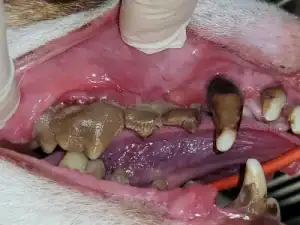

This is the end stage of gum disease with enormous concretions of calculus and severe infections around the tooth's roots.